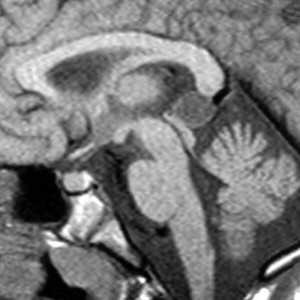

(а) На рисунке сагиттального среза показана классическая нейроэнтерическая киста (НЭК). Внутричерепные НЭК чаще всего обнаруживаются вблизи средней линии, кпереди от ствола головного мозга.

(б) Нейроэнтерические (эндодермальные) кисты в основном выстланы многорядным призматическим эпителием с большим количеством реснитчатых клеток. Отмечается вариабельное число муцин-секретируемых бокаловидных клеток.

Нейроэнтерическая киста (НЭК) представляет собой порок развития эмбриона, возникающий в результате персистирования нейроэнтерического канала, соединяющего эмбриональную кишку и развивающуюся невральную трубку. В результате незаращения канала формируется кистозная полость, стенка которой выстлана кубическим или цилиндрическим эпителием и содержит муцинпродуцирующие клетки [1].

Впервые эта патология описана Kubie в 1928 г., а затем Puuseep в 1934 г. и в настоящее время имеет несколько синонимов: энтерогенная киста, кишечная киста, киста энтодермального синуса, тератоматозная киста, интестиома, архэнтерическая киста [2]. По данным M. Greenberg [5], НЭК наиболее часто выявляются в первой декаде жизни человека, однако могут диагностироваться в любом возрасте и с одинаковой частотой встречаются у женщин и мужчин [3—5]. НЭК составляют менее 1% всех объемных образований спинномозгового канала и чаще локализуются на верхнегрудном и шейном уровнях. В мировой литературе, по данным A. Osborn [3, 4], в 2004 г. описано только 35 случаев интракраниаль-ной локализации, а в издании 2010 г. — уже 75 случаев. Интракраниальные НЭК располагаются преимущественно на вентральной поверхности ствола головного мозга (препонтинные, премедуллярные), однако возможно их наличие в мостомозжечковом углу, большой затылочной цистерне [1, 2, 6].